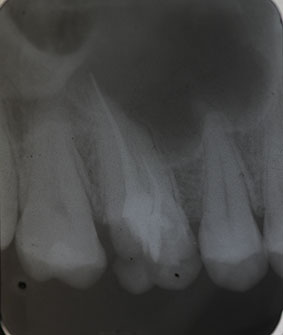

Nach erfolgter Information über die vermutete Prognose unternehmen wir den Versuch, das frakturierte Instrument darzustellen. Nach Entfernung der Aufbaufüllung werden die Kanaleingänge dargestellt (Abb. 2). Es zeigt sich, dass neben dem distovestibulären Kanal auch ein vierter Kanal (mb2) vorhanden ist. Die Darstellung der Wurzelkanaleingänge erfolgt in unserem Haus mit dem Aufsatz 1R des Tigon+. Dank der Abwinkelung des Instruments profitiert man von einer sehr guten Sicht auf die Behandlungsstelle. Zudem erlaubt es ein schnelles und gezieltes Abtragen von Dentin, ohne dabei den Zahn unnötig zu schwächen.